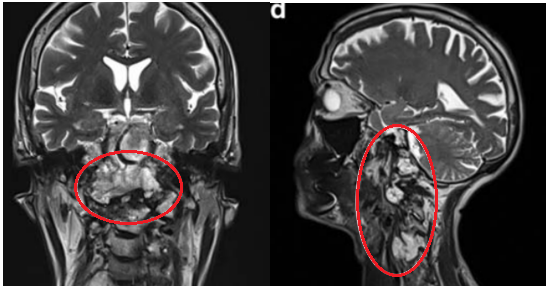

2019年初随访MRI,显示脊索瘤复发,颅颈交界区脊索瘤病变大小为51.3×74.3×25.9 mm,脊索瘤已经引起C2椎体病理性骨折及C1水平脊髓压迫,伴随C1右侧方、C1前后弓、C2椎体侵犯,齿状突后移和C1水平的侧向移位。肿瘤侵袭上三分之一的髁突和斜坡水平。肿瘤侵袭延伸至C5-C6水平,在椎前间隙浸润延伸,并压迫C5和C6神经根,并包裹椎动脉椎动脉的V2段。

▼图a-b术前MR显示颅颈交界区巨大脊索瘤,51.3×74.3×25.9 mm大小,浸润性生长。

▼图显示脊索瘤向周边浸润生长,下至C5-C6水平的脊髓瘤侵犯浸润。